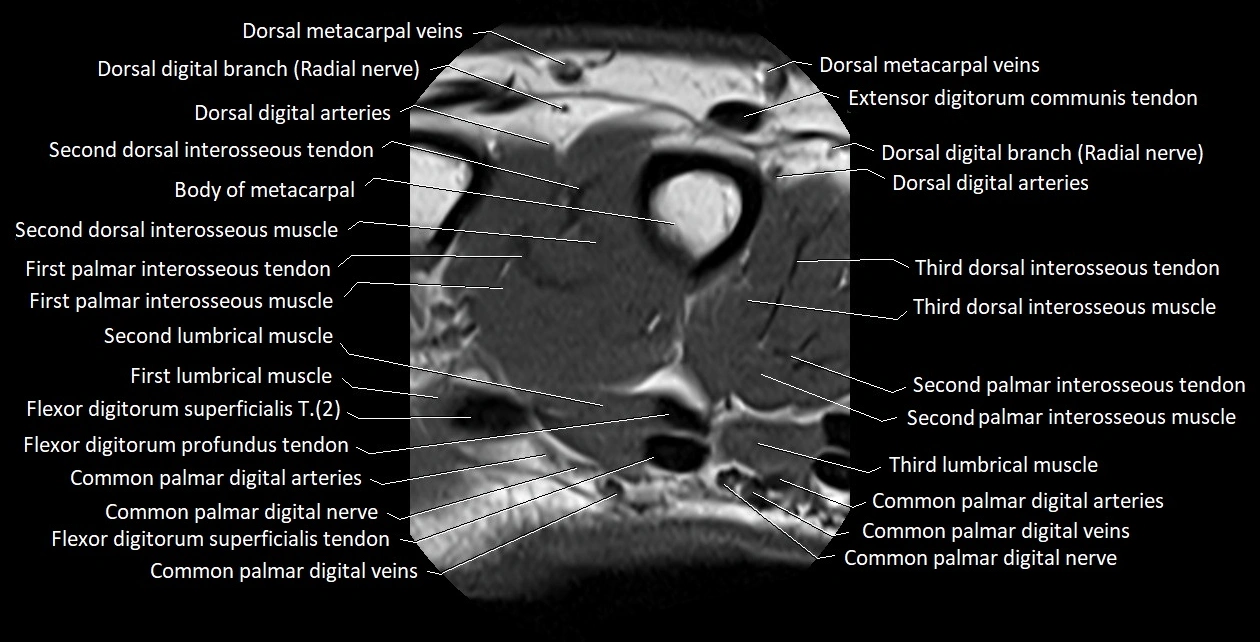

MRI images